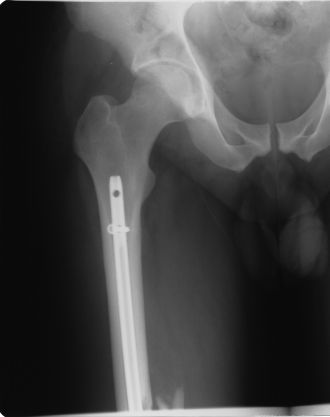

QuoteAt any rate- I must respond to Titanium Legs as I feel like he may be in the dark on something.....

Oh, I'm quite aware of what's in my x-rays. If you're really lucky, and maybe ask really nicely, I'll send you the very clear side view

QuoteSorry TitaniumLegs, its funny what you can see in an xray, unless of course its yours.

Oh, I think it's funny, too. Those x-ray tables and rooms are really cold!!

Lieutenant Dan!!!!

You got new legs! .... Magic Legs!